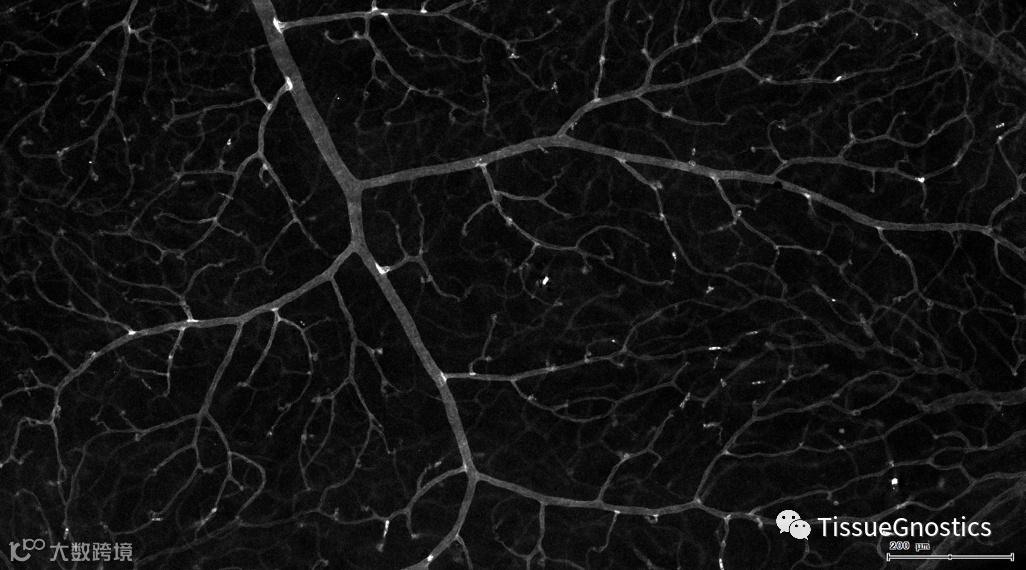

视网膜血管作为人体内唯一可以进行非创伤直接观察的深层微血管,其生理状况的检查对高血压、糖尿病、动脉硬化等心血管疾病的诊断、治疗评价具有重要意义。

一般而言,眼底图像通常都是通过激光扫描成像进行采集,但是由于眼底可观测的视野往往是很有限的,一个患者的眼底信息需要多张扫描图像才能完全显示出来。这种局限性大大不利于病情进行全面的、细致的诊断。Tissue Cytometry全景组织流式定量分析技术进行全景图像获取,在单细胞、组织结构、细胞空间信息等多个层面进行定位、定性、定量分析。从而更好的对病变区域进行有针对性的跟踪观察和全面分析。

视网膜荧光样本中小胶质细胞胞体、神经纤维识别、血管识别、血管斑点识别、神经元与血管的距离分析。

5. 识别血管的Texa Red染色区域面积及强度。

血管识别:根据Texa Red通道进行识别,并去除面积小的及非同一焦面的血管,仅对确定的清晰的同一焦面的大血管进行面积统计。